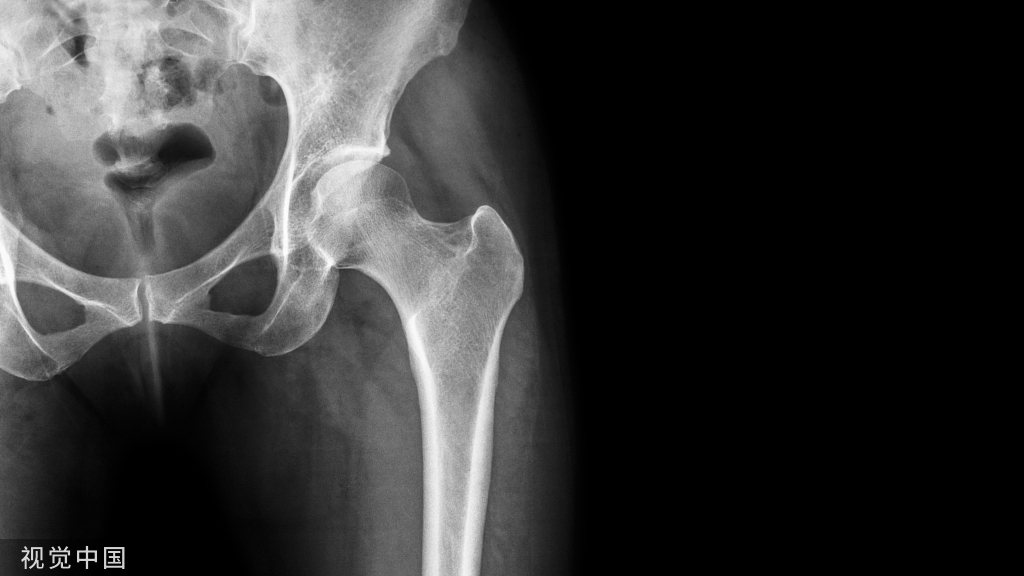

3.股骨粗隆间骨折